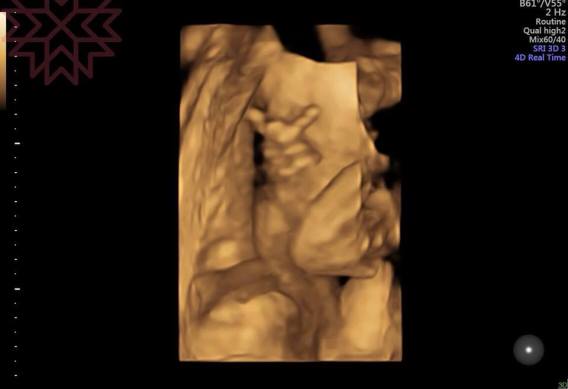

像這個寶寶在肚子裡就會比中指

所以出生後就會比較兇狠嗎

別鬧了啦